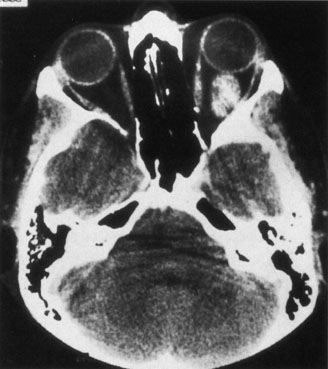

Contrast-enhanced CT of the orbits with direct and coronal cuts is the radiologic study of choice for these patients.45 A well-demarcated, encapsulated oval or rounded mass is revealed, which is typically intraconal in the lateral part of the middle third of the orbit (Fig. 5) but occasionally may extend to the extraconal space.42 Septa within the tumor may be apparent on high-resolution CT. The posterior pole of the globe frequently is indented by the rounded anterior margin of the tumor.42 The optic nerve typically is displaced rather than surrounded by the tumor. Subtle outward bowing of the lateral orbital wall or increase in orbital size may be present, consistent with a long-standing, slowly growing mass lesion.10,42 Enhancement with intravenous contrast occurs and may be homogeneous or inhomogeneous.10,45 Rarely, cavernous hemangiomas may occur as an intraosseous tumor within the orbital or facial bones.42,53–55 Although usually an isolated intraorbital lesion, multiple lesions in one orbit occurred in 8 of 164 (5%) patients of three combined large studies,10,42,45 and bilateral multiple cavernous hemangiomas also have been described.56 In contrast to patients with venous flow malformations in which phleboliths are common, phleboliths are rare in cavernous hemangiomas. Three large studies comprising 164 patients with cavernous hemangioma all reported that no calcification was detected within the tumor.10,42,45If the diagnosis is still unclear or if better definition of details and localization of the lesion is required, then MRI should be performed. Magnetic resonance imaging demonstrates nonspecific characteristics of a lesion isointense to muscle and gray matter on T1-weighted images and hyperintense on T2-weighted images (Fig. 6).57 The lesions show initial central patchy enhancement, which fills up homogeneously within 20 to 60 minutes.58 If ultrasonography is performed, B-scan ultrasonography shows a well-circumscribed mass with a sharply defined anterior acoustic border.23 A-scan ultrasonography shows high reflectivity of the echo signals resulting from the multiple blood-filled vascular channels, regular internal structure with a higher anterior and posterior spike marking the capsule, and moderate sound attenuation (angle of decrease of the echo spike within the lesion).24 Arteriography is not indicated.

Fig. 5. Cavernous hemangioma. Contrast-enhanced axial computed tomography scan shows a well-demarcated, oval intraconal mass in the lateral part of the middle third of the orbit. Note the enhancement within the lesion, which in this instance is inhomogeneous, but can also be homogeneous.